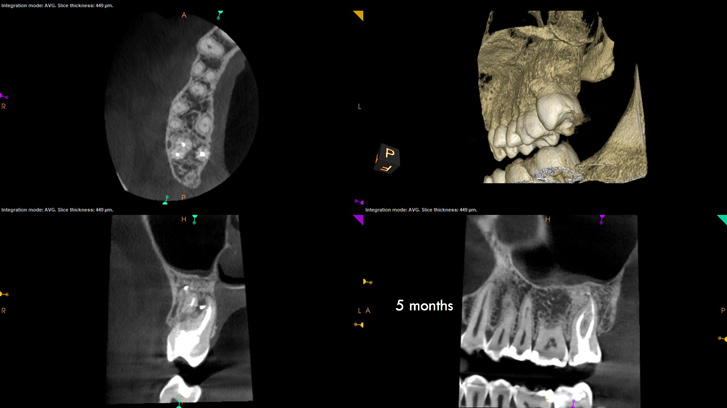

The second case study is that of a healthy 88-year-old woman who presented with significant bone loss on the mesial and apical aspect of tooth No. 18, which would suggest potentially a vertical fracture in the tooth (Figure 9 and Figure 10). The clinician had initially recommended extraction, which they informed the patient would likely be the best course of action, especially given that she had plenty of bone anterior to the tooth to place implants. When the recommendation of extraction was made to the referring dentist, he had some resistance because both he and the patient were interested in saving the tooth. Although the clinician initially stood firm on the recommendation, he received a call from the general dentist about a month later. He further expressed their desire to save the tooth, and he asked if the endodontist thought the new technology, the GentleWave Procedure, could be a solution. The informed consent was obtained and the patient was scheduled for treatment. Because the canal was quite calcified apically, a defined working length could not be determined. Obturation was performed using warm vertical condensation of gutta-percha.

As indicated in Figure 11, the mesial aspect of the distal canal was never touched by instruments, yet he was able to clean, evidenced by the postoperative image. In the past, a case with this level of difficulty would have required at least two appointments, with an interim medication of calcium hydroxide, but the case was treated in a single-visit appointment.  As observed 7 months later (Figure 12), the patient returned completely asymptomatic, and complete bone healing had occurred that exceeded initial expectations.

Fig 9. Case 2: Significant bone loss on the mesial and apical aspect suggested a potential vertical fracture (Fig 9 and Fig 10). Radiographic images were taken immediately postoperatively (Fig 11) and 7 months postoperatively (Fig 12).

Fig 10. Case 2: Significant bone loss on the mesial and apical aspect suggested a potential vertical fracture (Fig 9 and Fig 10). Radiographic images were taken immediately postoperatively (Fig 11) and 7 months postoperatively (Fig 12).

Fig 11. Case 2: Significant bone loss on the mesial and apical aspect suggested a potential vertical fracture (Fig 9 and Fig 10). Radiographic images were taken immediately postoperatively (Fig 11) and 7 months postoperatively (Fig 12).

Fig 12. Case 2: Significant bone loss on the mesial and apical aspect suggested a potential vertical fracture (Fig 9 and Fig 10). Radiographic images were taken immediately postoperatively (Fig 11) and 7 months postoperatively (Fig 12).